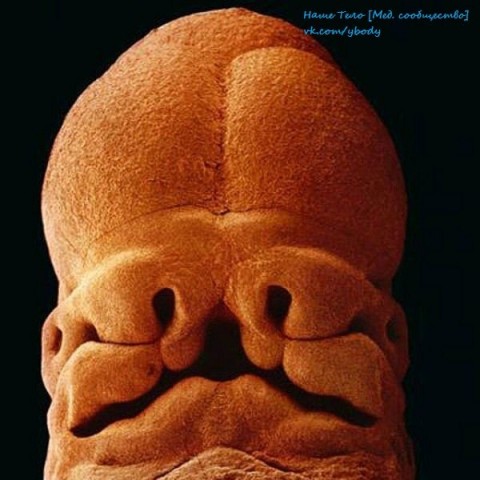

5 недель. Эмбрион, длина 9 мм, уже угадывается лицо с отверстиями для рта, ноздрей и глаз